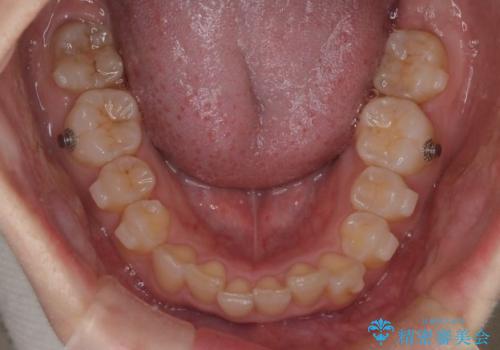

- 上の前歯の出っ歯と前歯の深い咬み合わせを治したいとのことで来院された患者様です。

上顎の歯は後方移動とIPR(歯と歯の間を削る)によって口元が引っ込むように、下顎は歯列全体の拡大とIPRによって上顎とバランスよく咬み合うように設計し、インビザラインにより治療を行うこととしました。

上顎歯列の後方への移動量が多く、右側の奥歯の咬み合わせを改善する必要もあったため、治療には長期間を要しました。